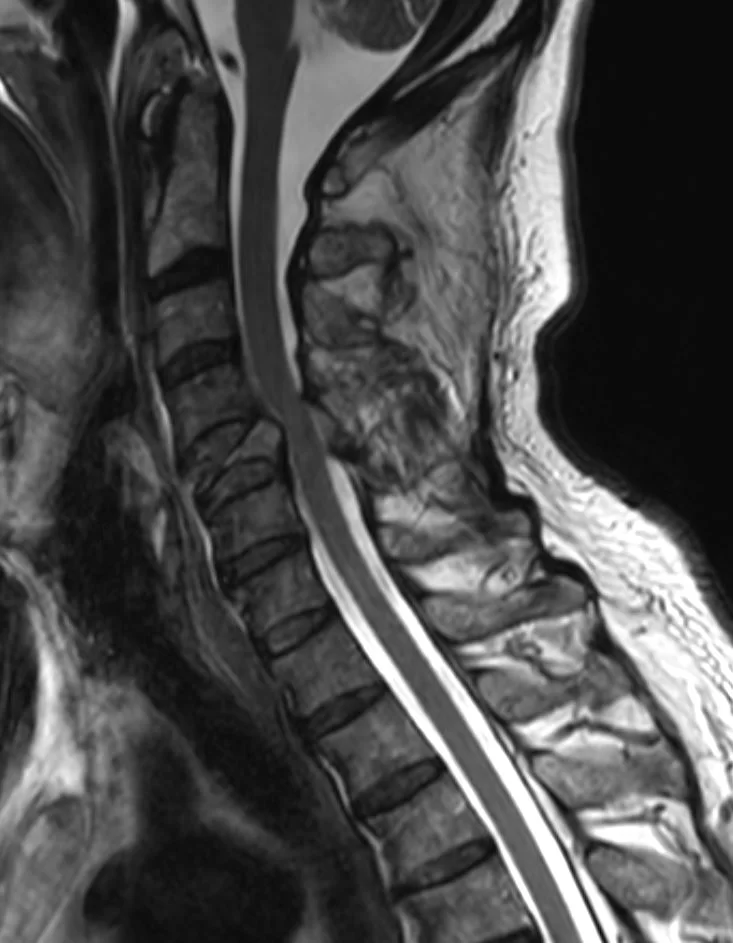

Ασθενής άδρας 60 ετών με εμμένουσα αυχεναλγία (3 εβδομάδες) και πάρεση του δεξιού άνω άκρου απο πενθημέρου.

Ο απεικονιστικός έλεγχος έλεγχος με μαγνητική και αξονική τομογραφία της αυχενικής μοίρας της σπονδυλικής στήλης ανέδειξε παθολογικό κάταγμα του Α5 σπονδύλου στα πλαίσια νεοπλασίας.